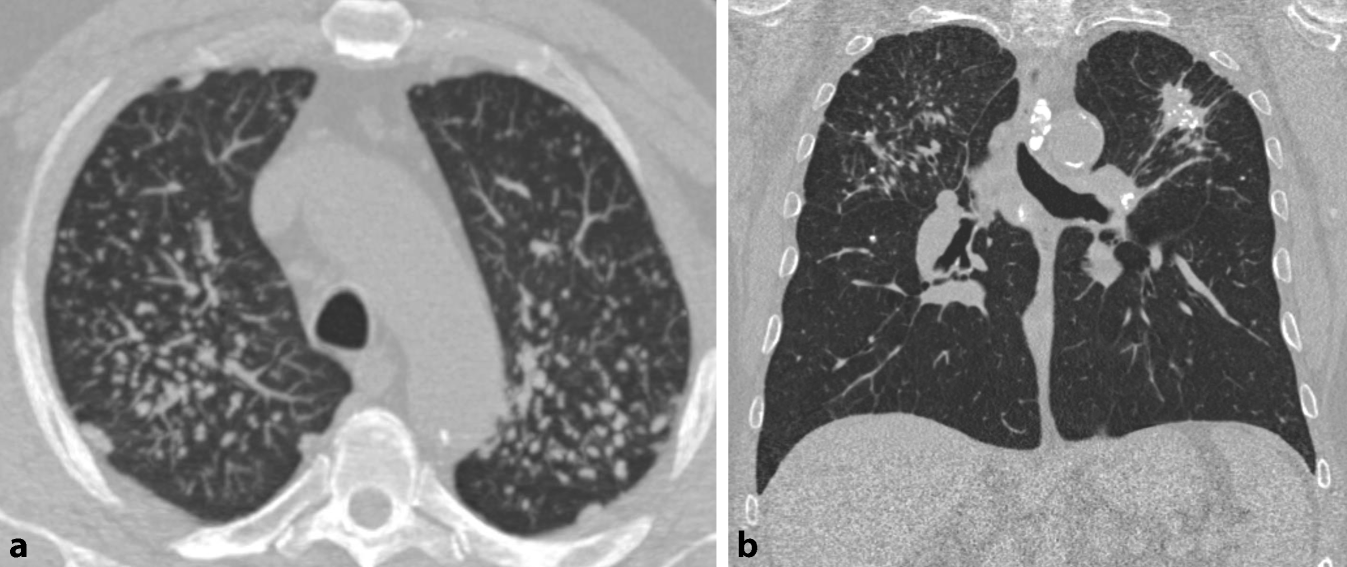

In der HRCT finden sich heute in Industrieländern überwiegend Parenchymmuster, die einem Initialstadium entsprechen. Das radiologische Bild ist zu diesem Zeitpunkt unspezifisch und nicht eindeutig einer Fibrose zuzuordnen (Tab. 6). Bei einer fortgeschrittenen Erkrankung sind differenzialdiagnostisch auch andere ILD mit UIP- oder NSIP-artigem Muster in Erwägung zu ziehen (Abb. 2). Bei bekannter Asbestfaserexposition kann in Deutschland eine fibrosierende Lungenerkrankung unfallversicherungsrechtlich dann mit überwiegender Wahrscheinlichkeit einer Asbestose zugeordnet werden, wenn bildmorphologische Kriterien einer asbestfaserbedingten Erkrankung der Pleura vorliegen und anderweitige Ursachen der pleuralen Verdickungen ausgeschlossen werden können.

Abb. 2

Asbestfaserbedingte Erkrankung von Lunge und Pleura

Benigne asbestfaserbedingte Erkrankung der Pleura BK 4103

Charakteristisch sind umschriebene spindel- oder tafelbergartige Areale mit einer hyalinen Fibrose der Pleura parietalis (sog. Pleuraplaques), die auch bei niedrigen Staubexpositionen ohne begleitende ILD auftreten können. Bei beidseitigem Auftreten sind sie bei Ausschluss anderweitiger Ursachen pathognomonisch. Eine Asbestfaserinhalation kann auch eine umschriebene oder langstreckige Verdickung der Pleura visceralis, eine Pleuritis, eine Hyalinosis complicata sowie Rundatelektasen induzieren (Tab. 7).